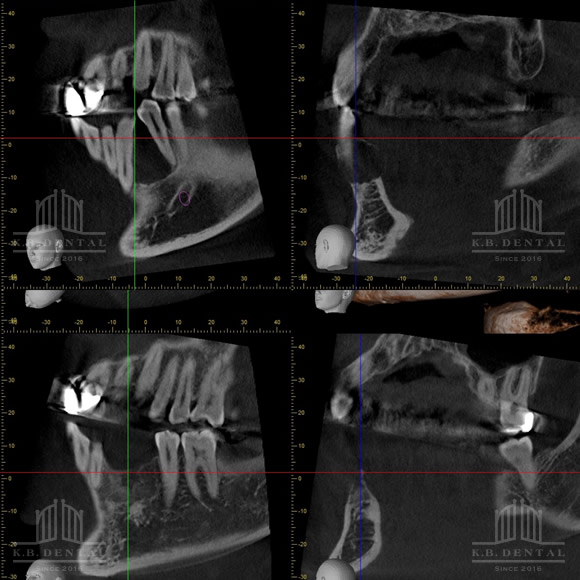

術後2年経過の最も典型的なエナメル上皮種です。再発率が非常に高いので最低でも5年以上の経過観察が必要となります。今回は摘出術と一部健常域まで辺縁切除(骨を削る)を行いました。

2枚目(CT)上:術前 下:術後 摘出部分に新生骨を認めます。